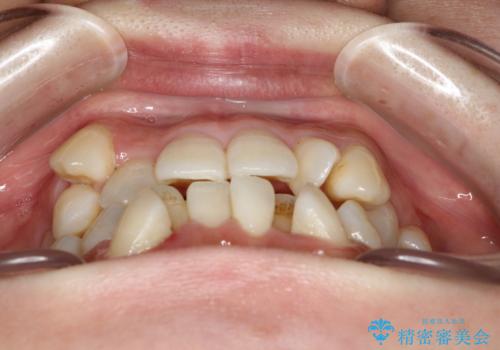

- 前歯の見た目の改善を希望され来院された患者様です。

初診時の歯並びの状態としては、上下に強いガタガタがある状態であり、それが原因で口腔内の清掃状態も極めて悪い状況でした。

スペースの不足量が著しく、上下左右の抜歯を伴うワイヤー矯正にて治療を行いました。

抜歯によるスペースを利用し、強いがたつきの改善を行いました。

また、左上の奥歯に関して親知らずの1つ手前の歯の状態が悪かったため、その歯は抜歯をし親知らずを利用して噛み合わせを作りました。